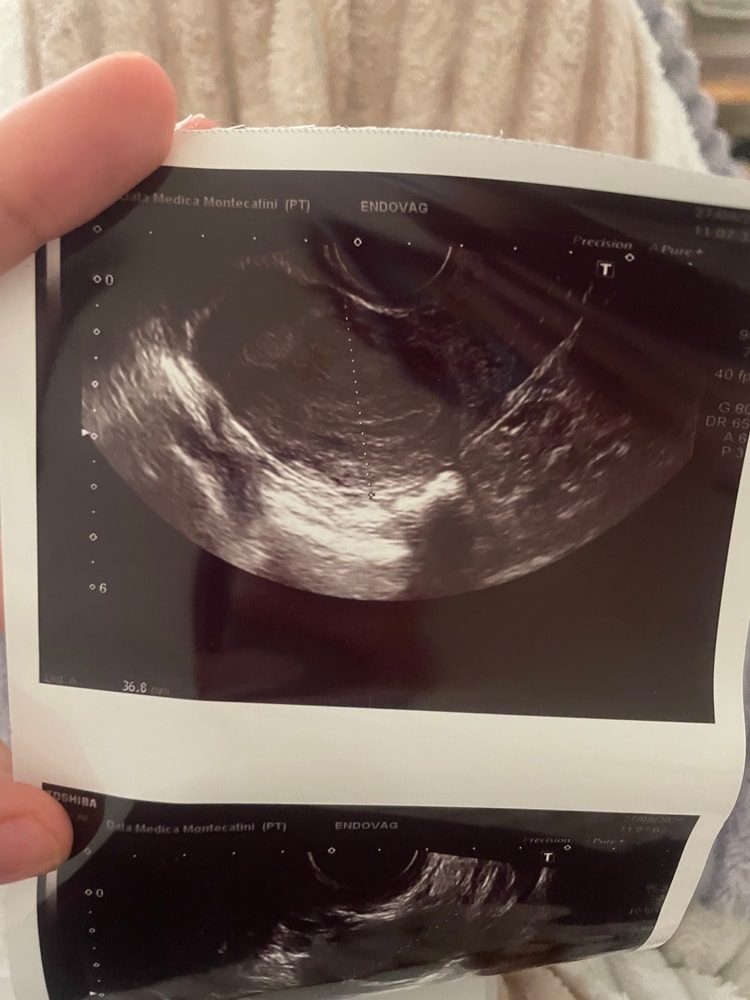

Девочки, подскажите, пожалуйста. Была на УЗИ и мне сказал врач что и на правом и налево яичники есть кисты ( 28*24 мм и 28*36 ) . Спросив какого они типа - он сказал что нужно наблюдать , пока Это не страшно , могут сами пройти . Вопрос такой , с кистами забеременеть нереально ? Они влияют на О ??? Хоть по графику бт она бывает, но …. капец ,аж 2 кисты 😭🤷🏻♀️

p.s. Сегодня поднялась бт , разболелась голова и появились выделения как обычно после О . Значит она случилась , и среди этих «кист» как минимум 1 доминантный фоликул был . Посмотрим дальше.